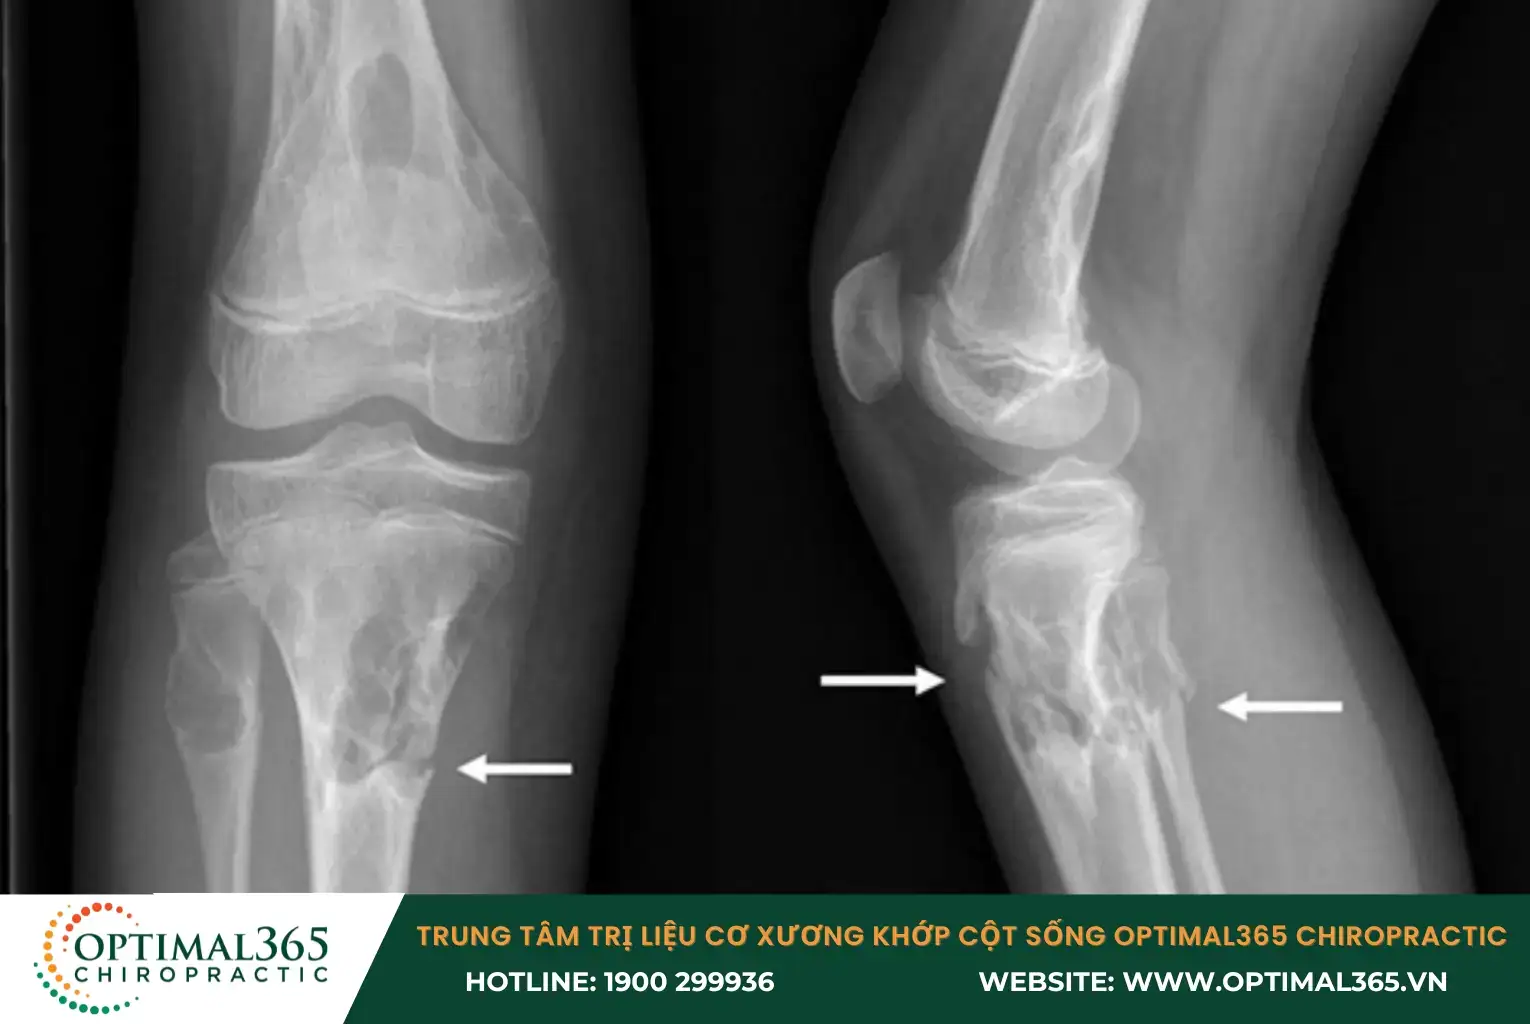

- Thoái hóa khớp sớm: Khi khớp gối mất đi sự ổn định do tổn thương dây chằng kéo dài, sụn khớp phải chịu áp lực lớn hơn, dễ dẫn đến sự mòn và thoái hóa sớm. Thoái hóa này thường xảy ra quanh vùng bánh chè, khoang trong và ngoài của khớp, gây đau và hạn chế cử động.

- Tổn thương sụn chêm: Sụn chêm là lớp đệm giữa các xương khớp gối, và khi dây chằng bị tổn thương, khớp gối mất đi sự ổn định, gây áp lực lên sụn chêm. Điều này có thể dẫn đến rách hoặc biến dạng sụn chêm, tăng ma sát trong khớp, gây đau nhức và làm giảm khả năng vận động.